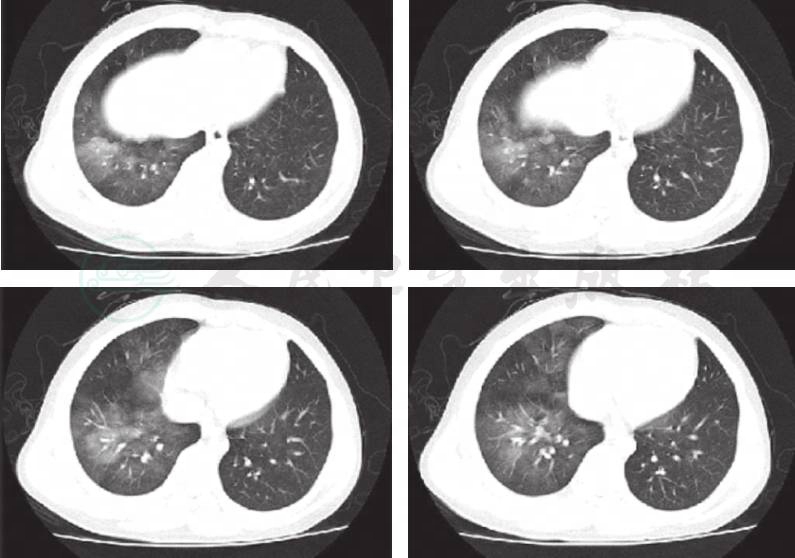

入院后急检血常规白细胞正常范围,予患儿头孢甲肟预防感染,同时完善病原学及相关常规检查。次日回报TB-Ab阴性;结核抗体阴性,肺炎衣原体抗体-IgM 阴性;肺炎支原体抗体-IgM 阴性,暂无结核、肺炎支原体及衣原体感染的证据;血红蛋白92g/L,提示轻度贫血。抗核抗体、抗nRNP抗体、抗Sm抗体、抗SS-A抗体、抗dsDNA抗体均阴性;抗线粒体抗体均为阴性;抗心磷脂抗体(ACA)、抗中性粒细胞胞质抗体测定(ANCA)及抗核抗体系列(ANA)均阴性,暂不支持系统性红斑狼疮等结缔组织病和ANCA相关性血管炎等引起的肺部损害。心电图正常,心脏超声正常不支持心源性咯血。入院第2天患儿再次咯血,量同前,检查血常规提示血红蛋白进行性下降提示肺部进行性出血,立即予患儿行支气管镜检查以明确出血部位,术中发现右肺下叶基底段可见鲜血涌出(图1),予1/10 000盐酸肾上腺素局部止血。因患儿出血量较大并急行肺部增强CT扫描提示:右肺中下叶见磨玻璃密度斑片影(图2),不除外肺血管异常导致出血,立即请介入科会诊,予患儿行支气管动脉造影术,术中发现血管略增粗扭曲,另见血管瘘(图3),予明胶海绵填塞后支气管动脉栓塞良好(图4)。夜间患儿再次出现呕血1次,约为50ml鲜血,患儿血氧饱和度下降,予患儿低流量吸氧,并予患儿垂体后叶素持续静脉滴注,联合凝血酶及酚磺乙胺止血并积极补液输血纠正贫血治疗。肺灌洗液结核菌涂片阴性,PPD阴性,结合支气管镜下的改变可除外肺结核;肺泡灌洗液未查到含铁血黄素细胞不支持肺含铁血黄素沉着症。患儿共住院治疗1周,无发热,未再次咯血及活动性出血表现出院观察。出院后电话随诊,患儿出院后无再次咯血,无反复感染及咳嗽史。

图2 右肺中下叶见磨玻璃密度斑片影。右肺中下叶渗出病变,结合病史考虑肺泡内出血